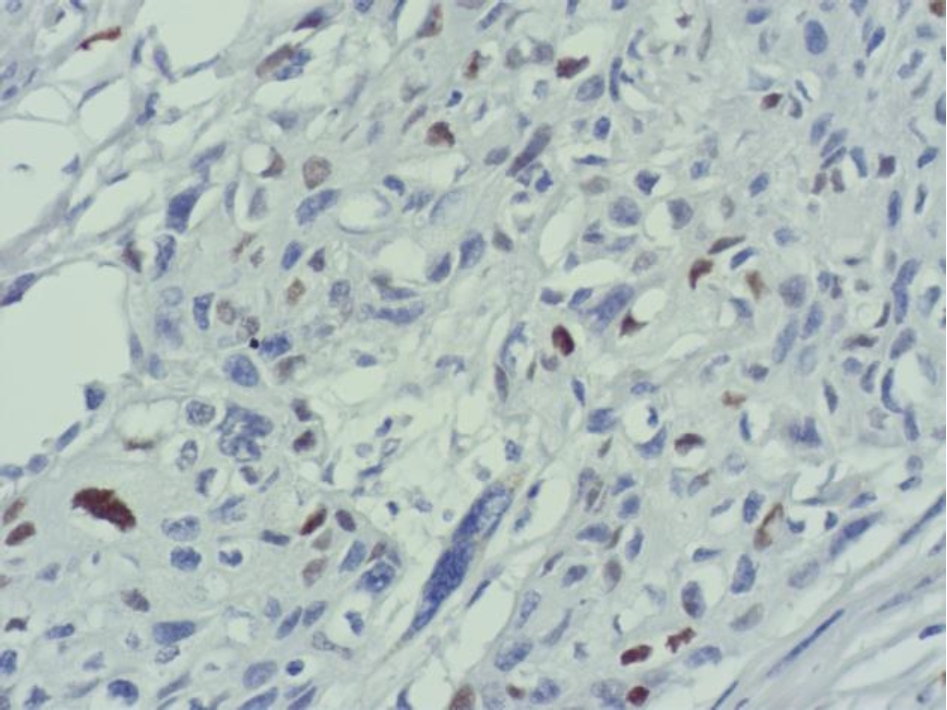

Во всех 19 исследуемых наблюдениях проведено дополнительное параллельное иммуногистохимическое исследование по выявлению экспрессии белков EGFR и Cyclin D1 соответственно, при этом диффузная, преимущественно умеренная экспрессия EGFR опреде-лялась в 17 (89 %) из 19 наблюдений (рис. 3), очаговая слабая экспрессия – в двух наблюдениях (11 %).

Экспрессия Cyclin D1 всех анализируемых наблюдений была очаговой, слабой и умеренной (рис. 4).

Рис. 4. Очаговая слабая и умеренная экспрессия Cyclin D1 в клетках плоскоклеточного рака языка. ИГХ окрашивание, ×400

Количество опухолевых клеток с амплификацией гена CCND1 в наших наблюдениях составило от 1 до 87, при этом гиперэкспрессии белка Cyclin D1 не определялось, экспрессия была очаговой, слабой и умеренной. По данным исследователей амплификация протоонкогена CCND1 при раке ротовой полости зависит от локализации, в частности, при раке языка составляет 88 [11] и 56,5 % [12], при плоскоклеточном раке щеки – 56 % [11], однако количество клеток с амплификацией не изучалось. В случаях разных категорий и степеней опухолевой дифференцировки определялась очаговая, слабая и умеренная экспрессия белка Cyclin D1, независимо от количества клеток с амплификацией протоонкогена CCND1. В работе исследователей также отсутствовала корреляционная связь между амплификацией CCND1 и экспрессией белка Cyclin D1 в случае плоскоклеточном раке полости рта [13].